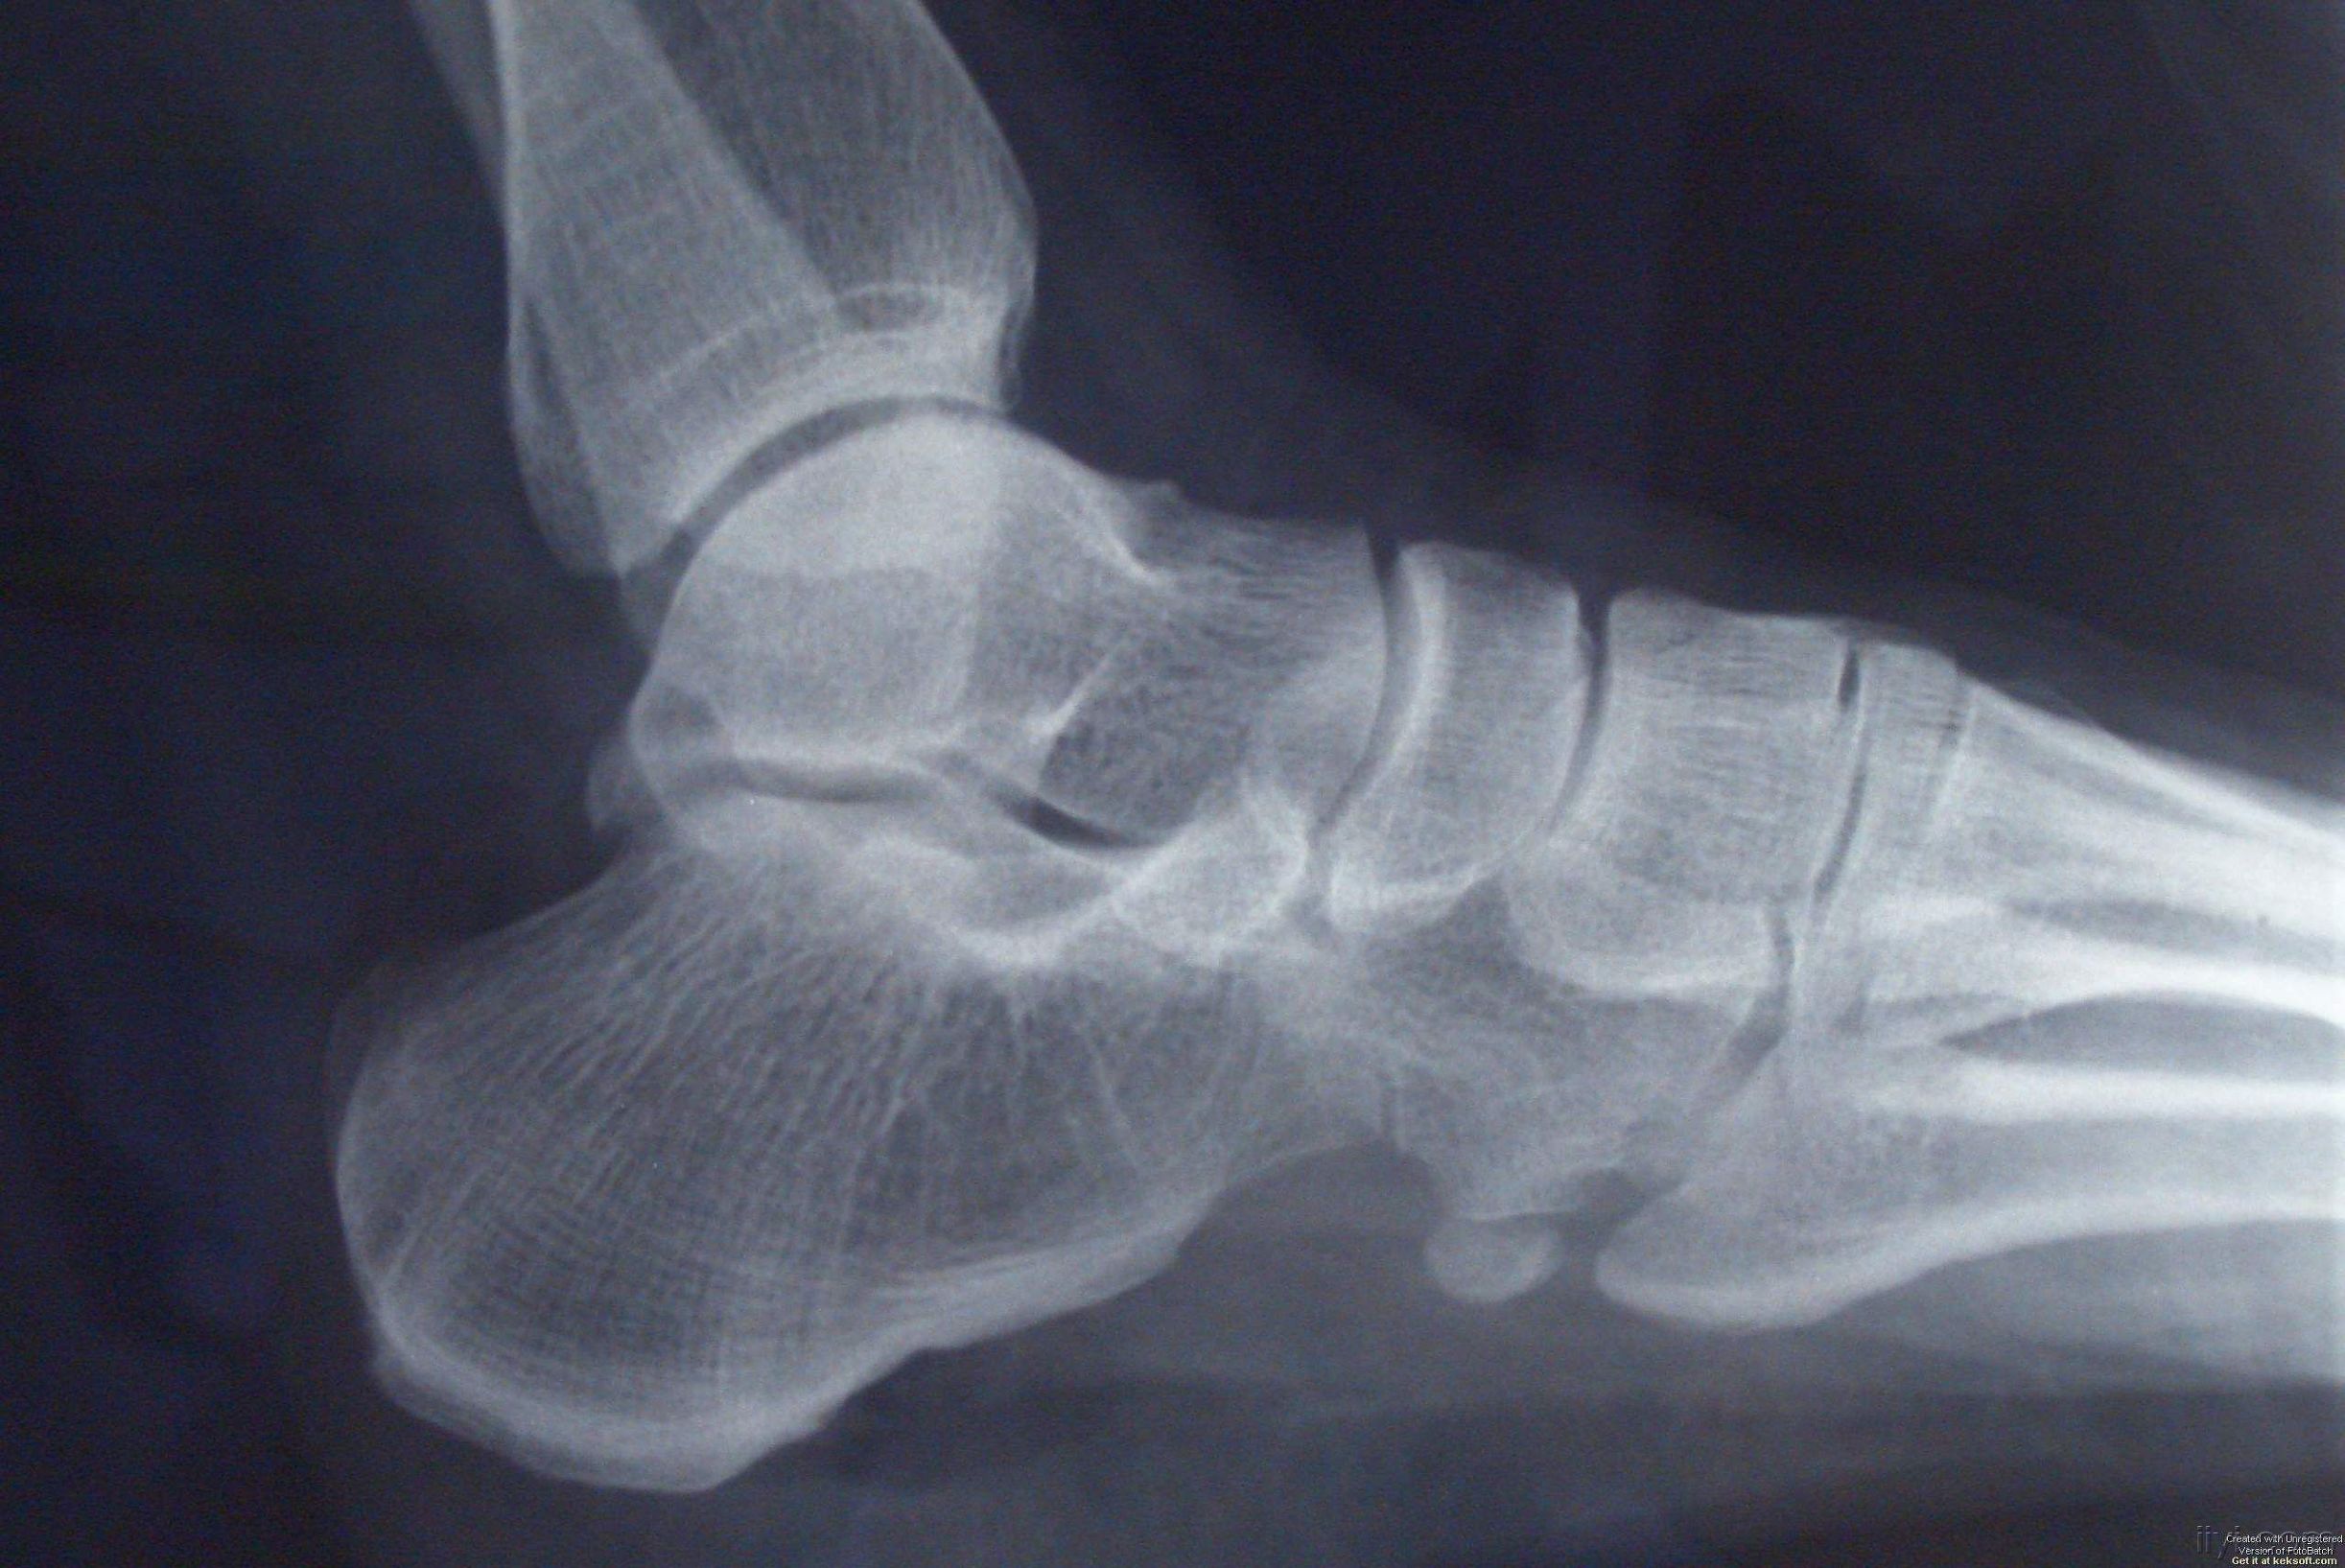

发生跟骨疼,若去拍X光片,可以发现跟骨结节处有大小不一的骨疣形成,但这并不是造成疼痛的直接原因。只是这些隆起的骨疣,更容易使局部组织劳损,产生无菌性炎症。或因过度的牵拉引发足底筋膜炎,引起跟腱紧张,带来疼痛。